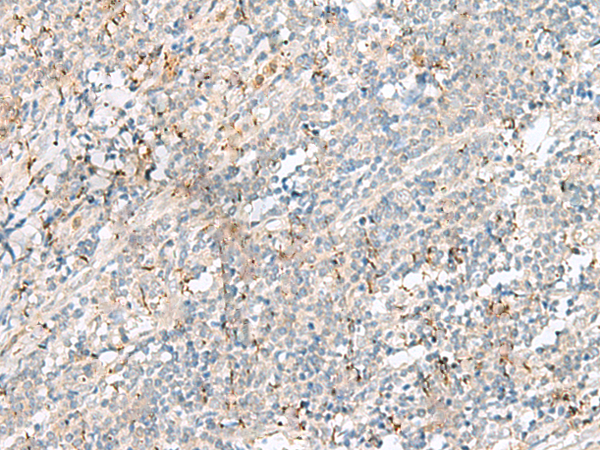

分类: 科研抗体货号: P09976别名: TIC; EFA6B应用: IHC反应种属: Human, Mouse